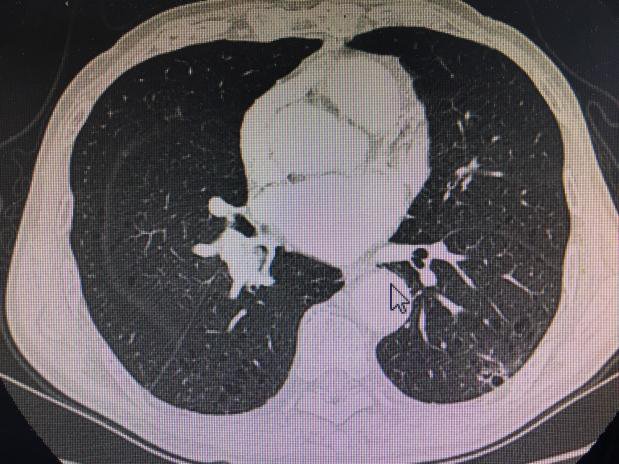

王大爷今年近80岁,因病住院,住院后行胸部强化CT提示右肺门占位:(见下图)

因病变部位靠近肺门,外周穿刺气胸、出血风险均较大,气管镜检查是最合适检查诊断方案,患者体质差,气管镜检查过程风险大,同时患者抵抗情绪严重,拒绝检查,不能取到病理,无法进行下一步治疗,家属焦急万分。肺病贾在金主任、于得海主任、麻醉手术科杜妍主任及科室医务人员联合进行讨论。